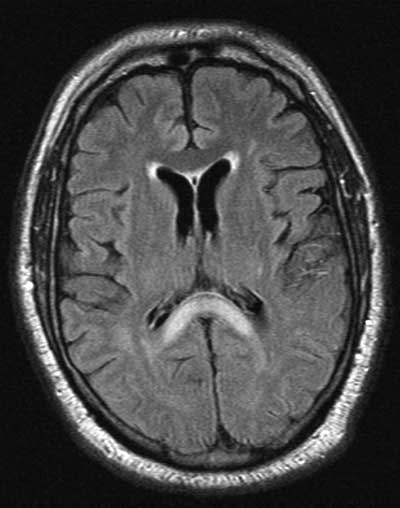

A middle-aged man with type 2 diabetes was brought to hospital with a history of loss of consciousness for an unknown period of time. He had refractory hypotension and hypoglycaemia. A magnetic resonance imaging scan showed an infarct in the splenium of the corpus callosum (Figure). The splenial infarct resembled a “boomerang”, which is characteristic.1

Strokes involving the splenium of the corpus callosum are associated with hypoperfusion,2 and can be seen in association with metabolic changes such as hypoglycaemia, hyponatraemia, hypernatraemia, and renal failure.1